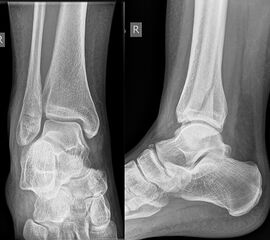

Die Standard-Röntgenaufnahmen des oberen Sprunggelenks bestehen aus drei Aufnahmen: der antero-posterioren Aufnahme (ap), der antero-posterioren Aufnahme mit Innenrotation des Unterschenkels von 20° („Mortise view“), sowie der streng seitlichen Aufnahme (siehe S2-Leitlinie Sprunggelenksfraktur). In der Röntgen-Bildgebung sollte neben den klassischen Frakturzeichen die Integrität der Syndesmose beurteilt werden. Dies erfolgt über die Beurteilung der Breite des lateralen und medialen Gelenkspalts („medial clear space“), des tibiofibularen Abstands 1cm oberhalb des OSG-Gelenkspalts („tibiofibular clear space“), bzw. der tibiofibularen Überlappung. Eine Verbreiterung des tibiofibularen Abstands über 5 mm oder die Erweiterung des medialen Gelenkspalts können Zeichen einer begleitenden Syndesmosenverletzung sein. (Abbildung 3) 6.

Liegt eine Fraktur des oberen Sprunggelenks vor, ist sowohl zur Entscheidung für ein konservatives oder operatives Vorgehen, als auch zur Operationsplanung, ein ausreichendes Verständnis der Fraktur und ihrer Morphologie notwendig. Insbesondere bei komplexen Verletzungen ist dafür die konventionelle Röntgenaufnahme in vielen Fällen nicht ausreichend. So konnten z.B. Black et al. zeigen, dass die operative Strategie zur Versorgung von OSG-Frakturen in 24% basierend auf einer zusätzlichen CT-Bildgebung relevant geändert wurden 7. Dies betraf die Lagerung, die Wahl des Zuganges und die Art der osteosynthetischen Versorgung. Besonders häufig änderte sich das Vorgehen bei Verletzungen des medialen (21%) und des posterioren Malleolus (15%). Darüber hinaus führten dislozierte (dislozierte Frakturen 31% vs. nicht-dislozierte Frakturen 20%) oder komplexe Frakturen (Trimalleolar-Frakturen 29% vs. Unimalleolar-Frakturen 10%) besonders häufig zu relevanten Änderungen des operativen Vorgehens. Die Computertomographie ist daher, insbesondere bei Bi- und Trimalleolar-Frakturen, essentiell für das Verständnis der Fraktur und somit für die Planung und Durchführung der Operation. In Abbildung 4 und 5 sind exemplarisch ein Röntgen- und ein CT Befund gegenübergestellt.

Luxationsfrakturen (Abbildung 7) sollten unter i.v.-Analgesie so schnell wie möglich reponiert werden, um Haut- und Weichteilschäden, Störungen der Durchblutung und Sensibilität, sowie den durch die Fehlstellung bedingten Druck auf den Knorpel zu verringern. Anschließend erfolgt die Ruhigstellung in einem gespaltenen Unterschenkelgips. Offene Frakturen, geschlossene Frakturen mit kritischen Weichteilverhältnissen, sowie hochgradig instabile Frakturen, die sich unter entsprechender Analgesie nicht zufriedenstellend reponieren bzw. retinieren lassen, stellen eine Notfallindikation dar. In diesen Fällen sollte die Anlage eines Fixateur externe erfolgen (Abbildung 8). Die definitive Frakturversorgung erfolgt zweizeitig nach entsprechender Konsolidierung der Weichteile. Eine Kompartment-Spaltung ist bei OSG-Frakturen nur sehr selten erforderlich.